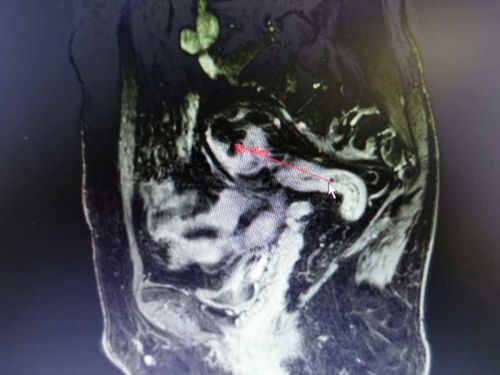

通过多项检查诊断技术全面评估肿瘤部位及患者全身状况, CT及MRI(普美显)提示患者乙状结肠癌并肝脏寡转移瘤,结直肠肛门外科、肝胆外科、放射科、肿瘤科、病理科开展晚期结直肠癌MDT讨论认为,患者乙状结肠癌肝转移合并不完全性肠梗阻,暂不适合术前新辅助化疗,有乙状结肠癌和肝转移瘤同时R0切除手术机会,但同时切除手术难度及风险增加。

乙状结肠肿瘤